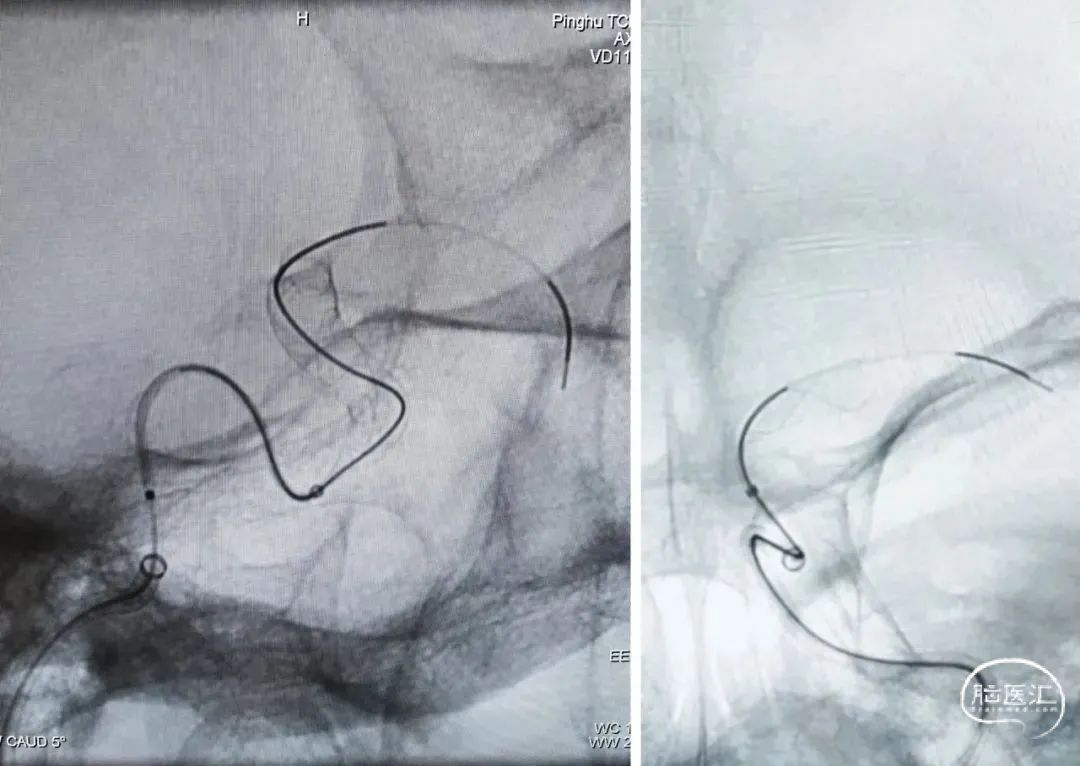

随即进行颈内动脉末端夹层动脉瘤的治疗,工作位置角度下,交换XT-27支架微导管,通过辅助支架至大脑中远端。

沿支架微导管输送Nuva®血流导向密网支架,待支架头端显影点与微导管齐平,支架输送到位,整体回撤微导管和支架至合适的锚定位置,在大脑中M1中段原位释放密网支架。

支架顺利打开,造形可见支架贴壁良好。

2.Nuva®血流导向密网支架创造性设计了输送系统释放段整体显影,清晰指示出血管真实走向,同时准确快速指示出可回收区域,为实现密网支架成功的释放提供了充分可靠的保障,有助于支架的成功释放。